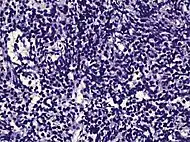

| Non acinar (or mixed acinar/ non-acinar) adenocarcinoma | Ductal adenocarcinoma | 3% to 12.7%[8][notes 1] | ![]() |

||||